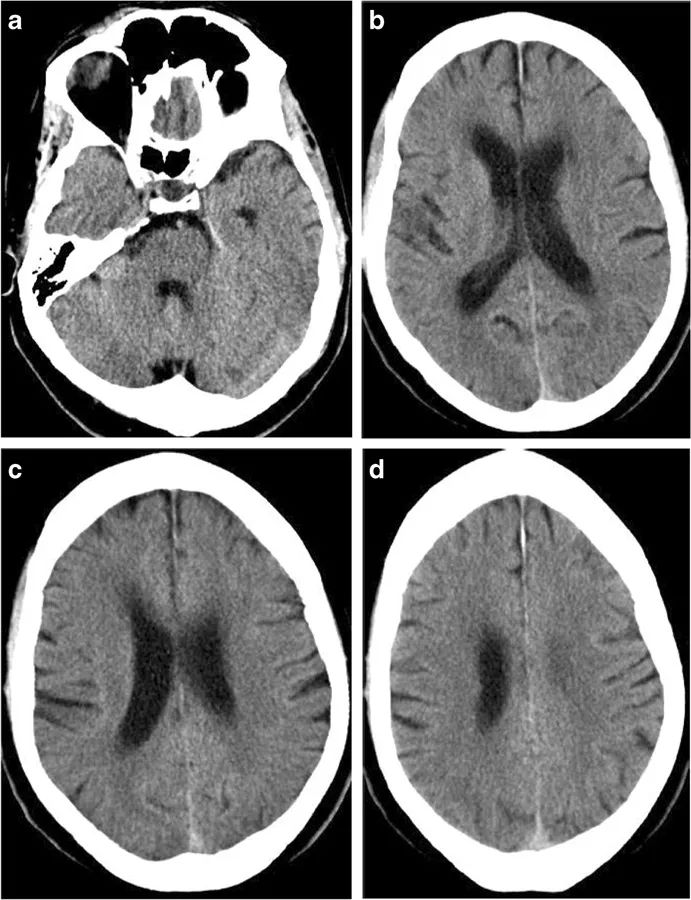

离子性脑水肿意味着严重缺血组织的含水量增加和肿胀。患者脑灰白质交界处变得模糊,CT上,由于额外的水流入细胞外空间,脑组织可出现均匀的低密度,对于局部缺血的病变,脑水肿低密度通常对应于受累的脑血管区域。MRI上则表现为T2/FLAIR的高信号,由于在急性和亚急性期的离子水肿之前存在潜在的细胞毒性水肿,通常也伴随有DWI上的弥散受限。

图2 恶性脑梗死的进展过程。在卒中发病的6小时内,CT仅显示额叶、岛叶皮质、颞叶、尾状核和豆状核的轻度密度减低(左);12小时后,可见大脑中动脉和大脑前动脉供血区域边界清晰的梗死区域(中);但没有占位效应。24小时后,病灶出现占位效应,中线移位(右)。